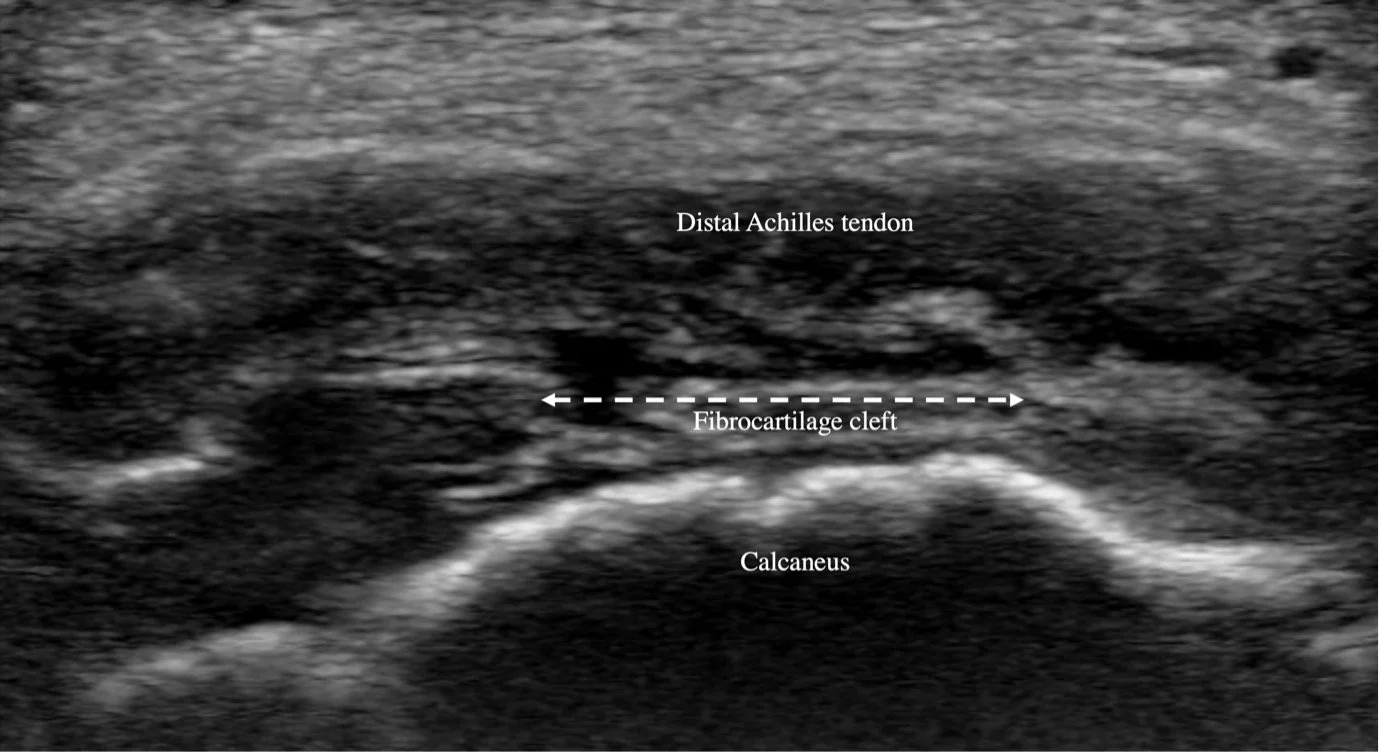

A 10-year-old boy, very active, presents with a 4-month history of heel pain, aggravated by activity. The onset coincided with a fall from his scooter. Is this Sever’s disease?

Have a look at the images and see if they match the generally accepted clinical picture of Sever’s.

Sometimes the reported onset may be a red herring. In this case, though all other history items pointed to Sever’s disease, it clearly wasn’t. When we examine children with Sever’s, there are seldom objective findings of injury, and “no cause for pain identified” ultrasound examination is reassuring. Sometimes however, we do find an injury or damage, and this usually necessitates further investigation or specific management. This case shows it’s well worth investigating clinical symptoms of Sever’s disease.